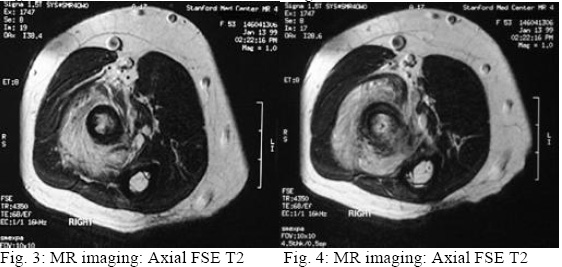

CHONDROSARCOMA, PROXIMAL RADIUS (Fig.1:-6:) History: 33 y/o male with pain and swelling about elbow. Findings: Plain films show an expansile lesion. The MR shows cortical destruction and soft tissue extension. Diagnosis: Chondrosarcoma, proximal radius.

Magnetic Resonance Imaging (MRI) can be helpful in differentiating between benign and malignant lesions

in several ways. First, the degree to which the tumor fills the medullary canal can be helpful (Figure 4).

Greater than 90% medullary involvement can be suggestive of chondrosarcoma, while the absence of 90%

medullary involvement of non-contiguous areas of cartilage within the bone can suggest the presence of an

enchondroma (Colyer et al., 1993). In addition, the timing and progression of gadolinium contrast

enhancement patterns may help direct a clinician toward or away from a diagnosis of malignancy (Geirnaerdt

et al., 2000). Early enhancement (within 10 seconds of arterial enhancement) may be seen in

chondrosarcoma but not in enchondroma. Many surgeons consider MRI critical for surgical planning because

it can illustrate the extent of tumor involvement in bone and soft tissues.